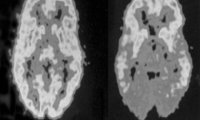

Немецкие ученые обнаружили связь нарушений работы головного мозга со склонностью к педофилии. Опыты проводились на 18 мужчинах, осужденных за сексуальное насилие над несовершеннолетними.